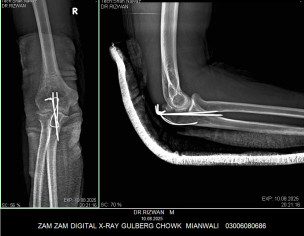

My husband had elbow surgery on 9th of August. I want to know about physiotherapy. When can we start physiotherapy so he can bend and extend his arm freely.Kindly guide us. If we start now will it effect joint or not. TIA